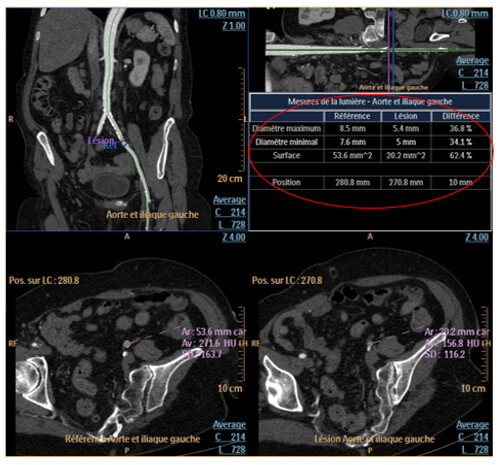

Stenosis Measurement

For stenosis quantification, you have to place the reference on the curvilinear or the stretched vessel image. Once positioned, verify the vessel’s contour for the reference and the lesion.

Stenosis Percentages

Stenosis percentages, maximum and minimum diameter and the surface are displayed in the following table.